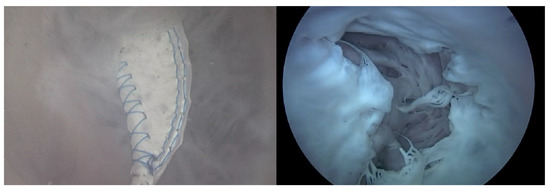

As can be observed in Figure 8, up to a flow rate of 60 cc/min from the TRG, the TV of Heart 1 maintained its normal functionality. This was validated by the endoscopic images, as displayed in Figure 7. An induction of TR was discernible on elevating the flow rate to 70–80 cc/min; however, upon turning off the TRG, the TV reverted to its normal function. This behavior was consistent, reaffirmed by subjecting the system to the same conditions thrice, with 10 min intervals between each test. Figure 9 presents a cross-sectional view of the spectrum graph from Figure 8 during the normal phase, while Figure 10 illustrates a similar cross-sectional view but during the abnormal phase. The two figures show a noticeable discrepancy in the amplitude values between 50 and 100 bpm. Specifically, the maximum amplitude values differ tenfold, registering approximately 2.4 mmHg in the standard phase and 25 mmHg in the abnormal phase.

Heart 2 in Figure 11, like Heart 1, represents a porcine heart exhibiting standard cardiac functions. It was employed to verify whether the heart simulator could consistently reproduce results comparable to those observed with Heart 1. Furthermore, experiments were planned with Pivot-TR installed. Figure 12 reveals results that closely resemble those of Figure 8. However, a distinct variation was observed with Heart 2. Unlike Heart 1, the TV displayed alternating patterns of normal and abnormal functionalities—a phenomenon subsequently termed the “Mixed phase”. A notable observation was that when the flow rate of the Harmonic Vibration Pump increased from 60 to 70 cc/min, only abnormal TV activity was evident.

Figure 7. Endoscopic image of Heart 1 (valve open, normal valve closed, abnormal valve closed).

Figure 11. Endoscopic image of Heart 2 (valve open, normal valve closed, abnormal valve closed).